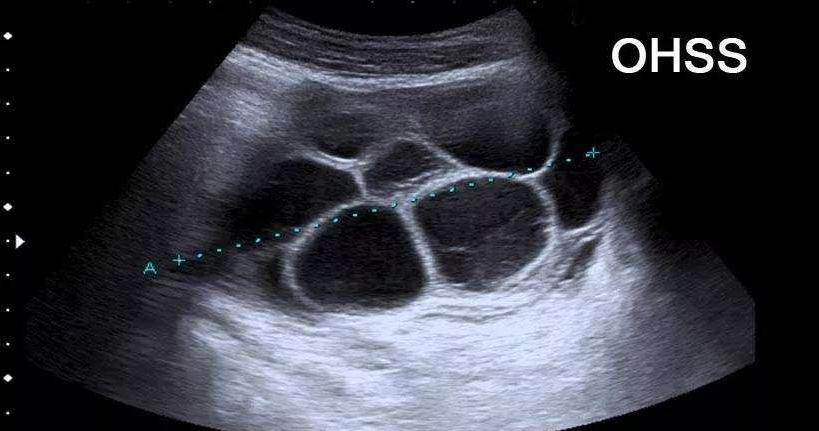

二、卵巢过度刺激综合征

使用促排卵药物,尤其是针剂型,有些人会有卵泡成长过多的现象而发生卵巢过度刺激综合征(OHSS)。其症状包括腹胀、腹痛、尿量减少、呼吸很喘等。

主要原因为卵巢分泌某些物质使得血管的通透性增加,而造成水份,电解质,蛋白质等部分流出血管外,而堆积于腹腔、胸腔,形成腹水或肋膜积水。超声检查可发现腹腔内有大量液体,以及卵巢肿大。

就医时应告诉医生有使用促排卵药物,以免被误认为卵巢肿瘤。大部分患者在1-2周左右就会恢复,但严重者可能持续一个月甚至更久,尤其是在怀孕时,因为怀孕可能会使症状加剧。每天要有适当的小便量,如果症状较严重或小便量较少时需住院治疗,以减轻症状。